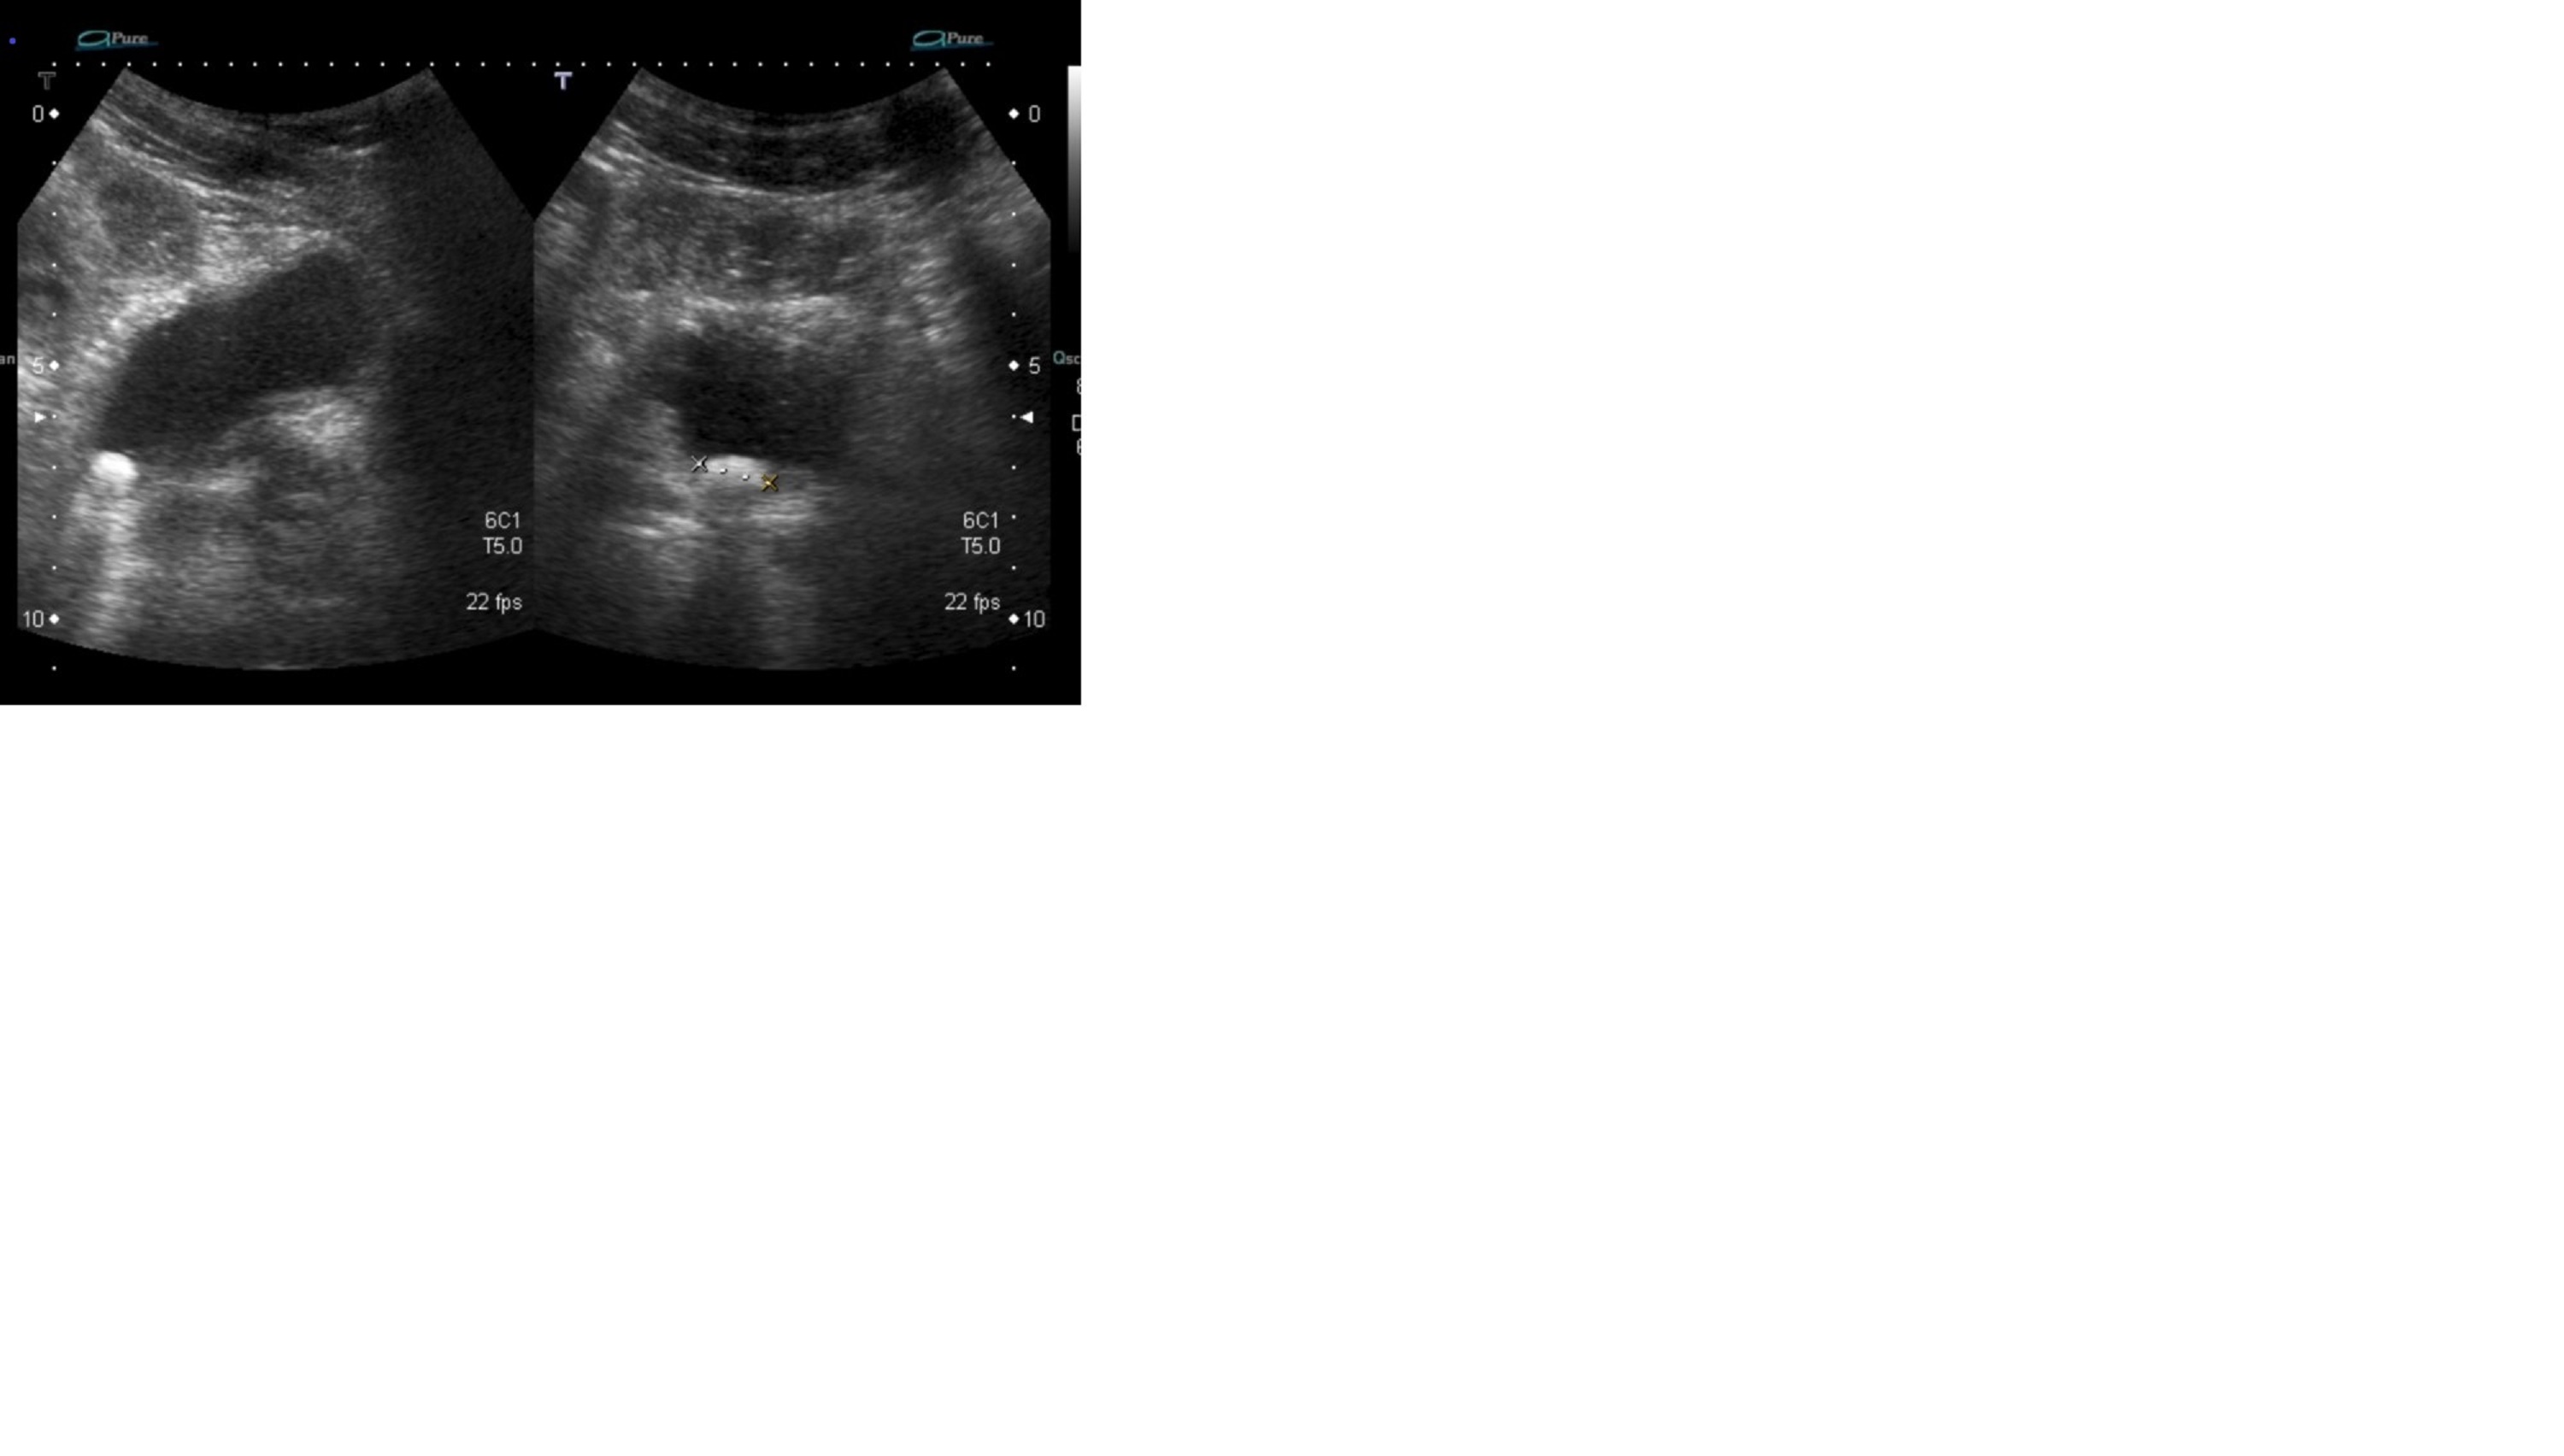

Se realizó una ecografía al paciente que mostraba la siguiente imagen:

Presentaba una litiasis vesical de 1,5 x 1 cm y un residuo post miccional de 150 mL. Fue intervenido realizándose al mismo tiempo resección de la próstata y resolviendo su problema.